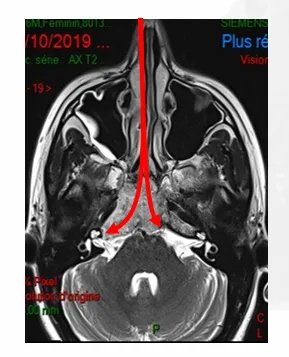

▼根据肿瘤的位置选择不同角度的一些角度镜图片

鼻腔末端是蝶窦,这扇门是蝶窦的前壁。在进入这扇门之前,不应该接触鼻腔内的任何组织。一旦进入蝶窦,可以往上、下、旁边不同方向进行手术操作。为什么呢?因为福教授有角度镜。

在通道很窄的手术中,需要使用有角度的弯曲的仪器,旋转可以从侧面深入到角落。福教授用30度、45度甚至70度(换数字)的内镜,目前他们也正在努力的开发这方面的器械。对于保护重要神经、更加准确移除肿瘤、灵活操作入路角度镜等都有重要作用。